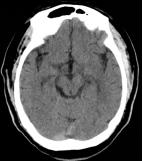

当地医院行颅脑CT未见明显异常,考虑为急性脑梗死,给予阿替普酶静脉(78.3 mg,按照0.9 mg/kg)溶栓治疗,溶栓结束后患者症状未见明显好转,意识水平逐渐下降。

术前影像

向右滑动查看更多

图1急诊颅脑CT